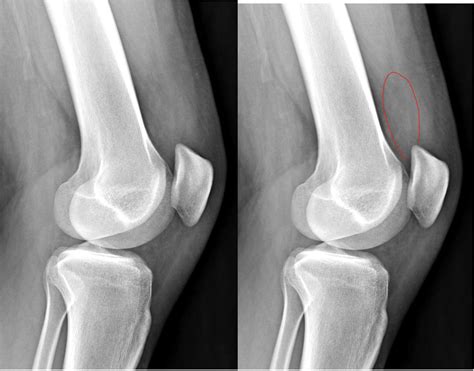

• Swelling: The affected joint appears larger than normal due to fluid buildup.

• Imaging Tests: X-rays, MRI, or ultrasound may be used to visualize the joint and assess the extent of fluid buildup.